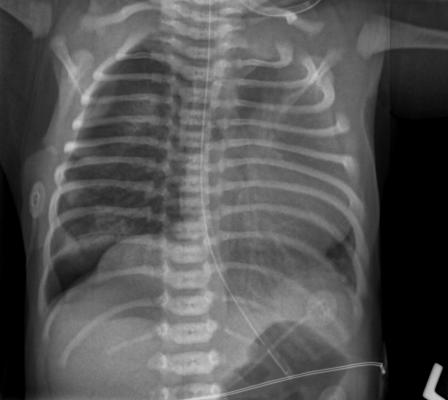

August 27, 2018 — The Radiological Society of North America (RSNA) has launched its second annual machine learning challenge. The RSNA Pneumonia Detection challenge invites teams to develop algorithms to identify and localize pneumonia in chest X-rays.

A machine learning data challenge is a competition among AI researchers to create applications that perform a defined task according to specified performance measures. The Pneumonia Detection challenge will be based on a publicly available dataset published by the National Institutes of Health (NIH) that has been carefully annotated by multiple expert reviewers. The RSNA Machine Learning Steering Subcommittee collaborated with volunteer specialists from the Society of Thoracic Radiology to annotate the dataset, identifying abnormal areas in the lung images and assessing the probability of pneumonia.